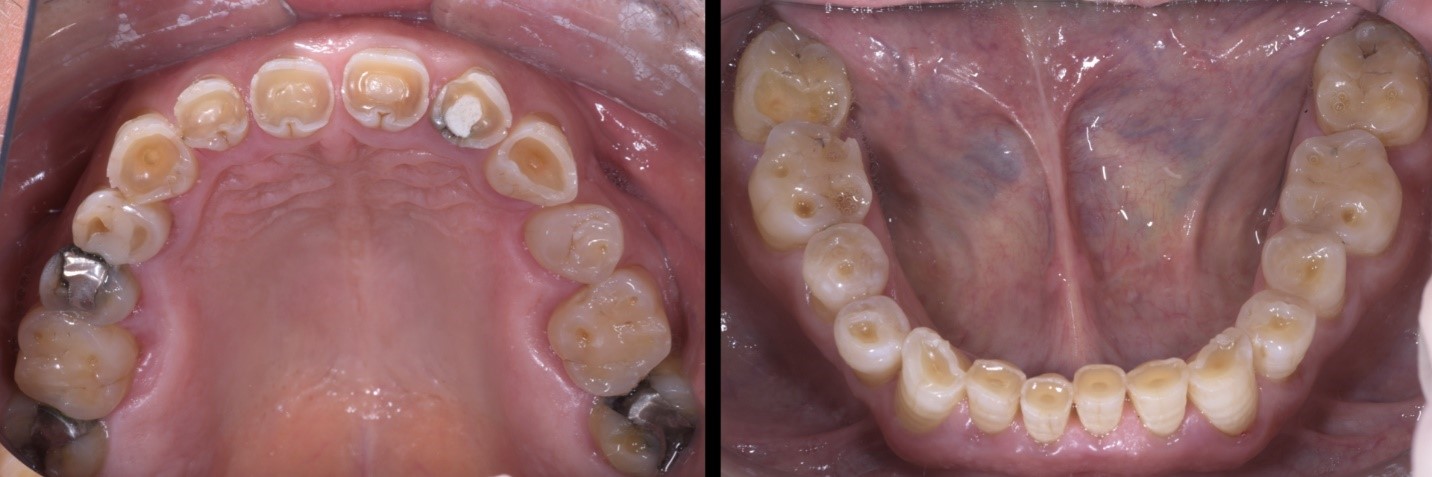

garrison-roberto-turrini

Fig. 2a e 2b

Dopo un attento studio del caso, si opta per una riabilitazione completa con rialzo della dimensione verticale di occlusione. Il rialzo calibrato della DVO viene testato mediante mock-up per un periodo di 2 mesi.